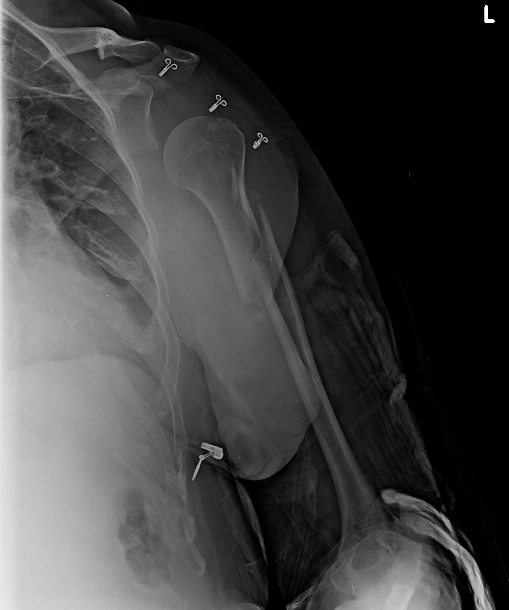

Frontal radiograph of the left shoulder. Non-displaced left greater tuberosity fracture. No intra-articular extension.

Frontal radiograph of the left humerus . Obliquely oriented proximal left humeral shaft fracture with half shaft width lateral displacement.